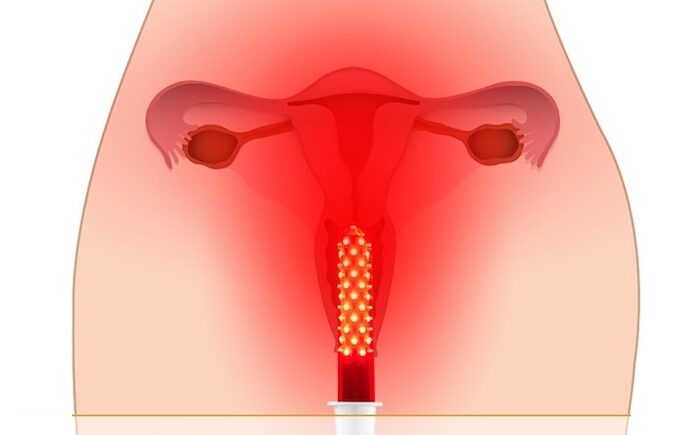

- Chequeos de Papanicolau y colposcopía para detección precoz de cáncer de cuello uterino.

- Procedimientos de ginecología estética y funcional: rejuvenecimiento vaginal, labioplastía, tratamientos con láser y PRP.